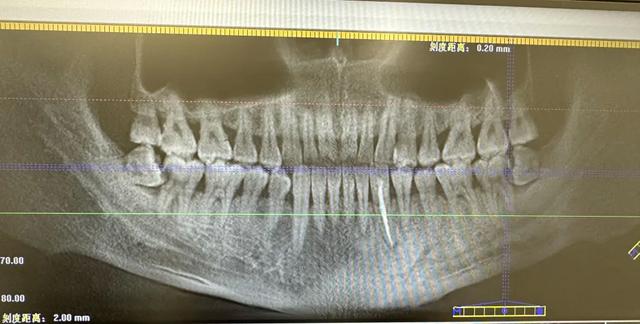

您下面智齒斜著長的,跟前面的第二磨牙經(jīng)常性食物嵌塞,把第二磨牙的鄰面蛀壞了,拍個片子看看吧。

您兩邊的智齒都把前面的第二磨牙頂壞了,治療計劃是拔除智齒,治療第二磨牙,要來好幾次了,費用也不低。

智齒是人類的第三顆磨牙,是人類口腔最后長出的牙齒,通常位于口腔最內(nèi)側(cè),從正中的門牙往里數(shù)剛好是第八顆,其萌出是正常的生理現(xiàn)象,一般會在17-25歲萌出,但個體差異較大,有的人可能在17歲之前就已經(jīng)萌出,也有人到40、50歲才長或終身不長。

智齒生長方向正常:如果智齒生長的方向比較正常,存在對頜牙,并且能夠與對頜牙形成良好的咬合關(guān)系,可以行使正常的咬合功能,則不用拔除。

完全埋伏且無癥狀的智齒:智齒完全埋伏于牙槽骨內(nèi)不再發(fā)育,并且與鄰牙牙周無相通,也沒有壓迫神經(jīng)引起的疼痛癥狀,可以暫時保留,不用拔除。

智齒阻生:阻生智齒是指智齒在萌出過程中受到阻礙,無法完全萌出至正常位置。這類智齒容易引發(fā)智齒冠周炎,且難以清潔,可能導致齲齒等問題,因此需要拔除。